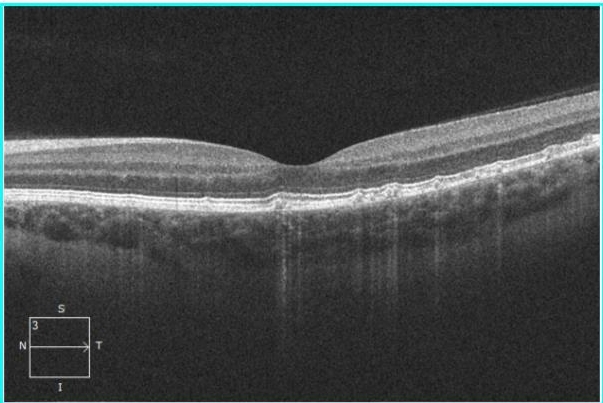

Вначале это маленькие круглые пятна, светлее окружающего их фона глазного дна, со временем приобретающие яркий желтый цвет. По мнению D.A. Newsome (1988), первая их диагностика возможна скорее ангиографически, чем офтальмоскопически. Авторы настоящей главы не разделяют эту точку зрения. Считается, что друзы, локализующиеся кнутри от диска зрительного нерва, или множественные, покрывающие почти все глазное дно, являются доминантными друзами. Как правило, их обнаруживают в центральной зоне и на средней периферии. В редких случаях друзы могут наблюдаться только на средней периферии и отсутствовать в центре. Возможно периферическое расположение друз, иногда с сетевидным пигментом, в связи с чем они напоминают ретикулярную дистрофию Сьегрена или «гроздь винограда».

Со временем размер и количество друз увеличиваются, они сливаются, кальцифицируются, приподнимают сенсорную сетчатку. В очень редких случаях количество друз может уменьшаться. Заметные изменения происходят и в пигментном эпителии, покрывающем друзы. Он истончается, теряет пигмент, появляются скопления пигмента вокруг друз. Эти изменения пигментного эпителия наблюдаются в макуле между друзами и могут приводить к атрофии клеток пигментного эпителия.

Друзы могут располагаться над и под базальной мембраной пигментного эпителия, иногда их находят и в хороикапиллярном слое. Как правило, друзы являются офтальмоскопической находкой, так как протекают бессимптомно, даже если локализуются в фовеа, в редких случаях больные жалуются на метаморфопсию. Острота зрения не снижается, дефектов в поле зрения не бывает.

Во время флюоресцентной ангиографии друзы начинают флюоресцировать в ранних фазах с постепенно нарастающей интенсивностью, которая в позднюю венозную фазу быстро снижается. Обычно ангиографически выявляют значительно большее число друз, чем при офтальмоскопии. Твердые друзы, даже в местах их скопления и кажущегося слияния, на ФАГ видны в виде отдельных гиперфлюоресцирующих точек. В редких случаях на флюоресцентных ангиограммах наблюдается гипофлюоресценция друз, обусловленная их кальцификацией или пигментацией.